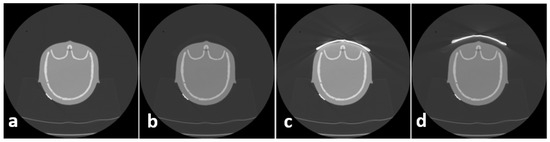

In order to overcome this disadvantage, the following approach proved to be successful at the authors’ institution: a 2.0 cm standoff foam is placed between the patient and BS to reduce artifacts in superficial areas. To assess the influence of BS as well as the influence of foam on image quality, CT scans were acquired in the following way: phantom alone, phantom + foam, phantom + BS, and phantom + foam + BS, as depicted in Figure 2. These scans were conducted only for the assessment of image quality; therefore, no dosimetric values were acquired.

Figure 2.

Protocol for quality assessment included 4 scans pro series: phantom (a), phantom + foam (b), phantom + bismuth shield (c), phantom + foam + bismuth shield (d).